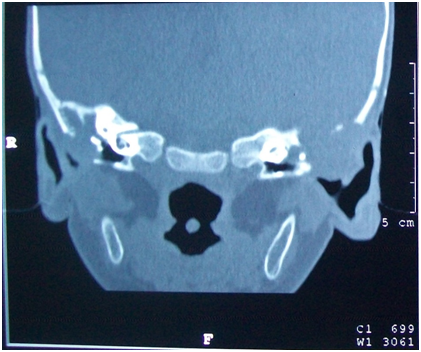

Urine routine examination was within normal limits. C reactive protein was 4.8 mg/dl (positive >0.6). A contrast enhanced computerized tomography (CT) scan of the temporal bone showed bilateral ottitis media with erosion of right side mastoid bone and right post auriclar abscess (Figures 2&3).

Figure 3 HRCT Temporal bone (coronal view) shows soft tissue density in bilateral middle ear, attic. There is also erosion of bilateral dural plate.